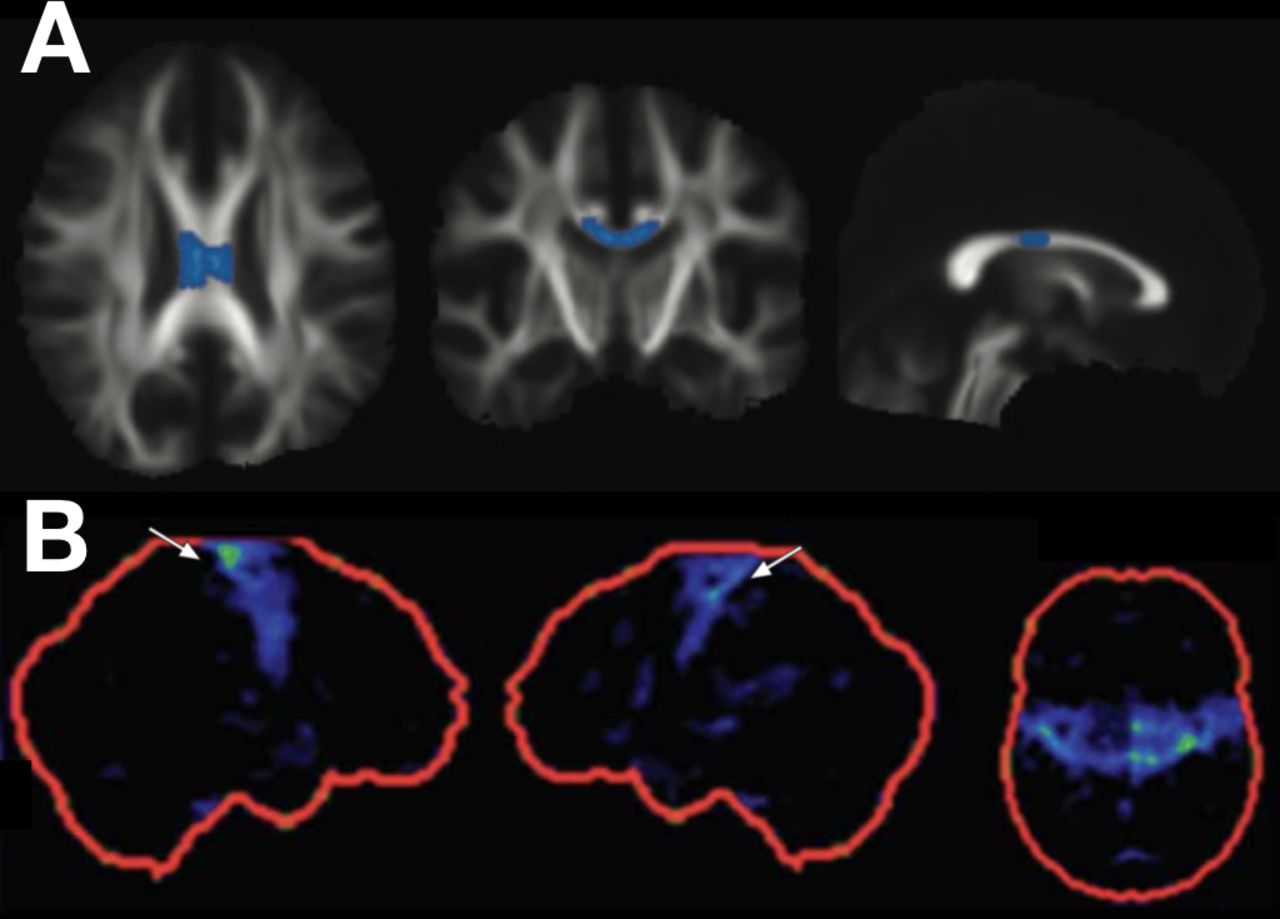

Figuur 1

Bevindingen inzake diffusietensor-imaging en fluorodeoxyglucose (FDG) positron-emissietomografie (PET) in gevallen van primaire laterale sclerose (PLS). De gemiddelde diffusiviteit in het middelste gedeelte van het corpus callosum is verhoogd in gevallen van PLS vergeleken met amyotrofische laterale sclerose (rij A, PLS- vs. ALS-groepbevindingen, geaccentueerd op axiale, coronale en sagittale beelden van het skelet van de wittestofwegen; met dank aan de auteur, zie Iwata et al). Focaal hypometabolisme kan worden vastgesteld in de primaire motorische cortices bij PLS (rij B, FDG PET z-scorebeelden in de rechter sagittale, linker sagittale en axiale vlakken; met dank aan de auteur, zie Claassen et al). Vooralsnog heeft geen van deze technieken voldoende sensitiviteit of specificiteit om ze op zichzelf toe te passen voor de diagnose van PLS.